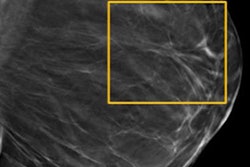

Breast density measurements calculated on full-field digital mammography (FFDM) and digital breast tomosynthesis (DBT) are comparable -- and so are median radiation dose values for dense breasts, according to Spanish investigators.

DBT has been shown to find more cancers and reduce recall rates when compared with digital mammography, whether or not a woman has dense tissue, according to the authors. But there has been concern that adding DBT to FFDM increases the radiation dose, a problem that can be exacerbated by dense tissue. To address that issue, some vendors have developed software that synthesizes 2D images from DBT exams, thus reducing the amount of radiation to which women are exposed.

Castillo-Garcia's group sought to compare breast density estimates from two measurement tools on FFDM and DBT and also analyze the impact of individual women's breast density values on mean glandular dose for both modalities. The team included 561 combination FFDM and DBT mammograms taken between November 2015 and January 2016 using Hologic's Selenia Dimensions system with C-View software, which generates synthesized 2D images.